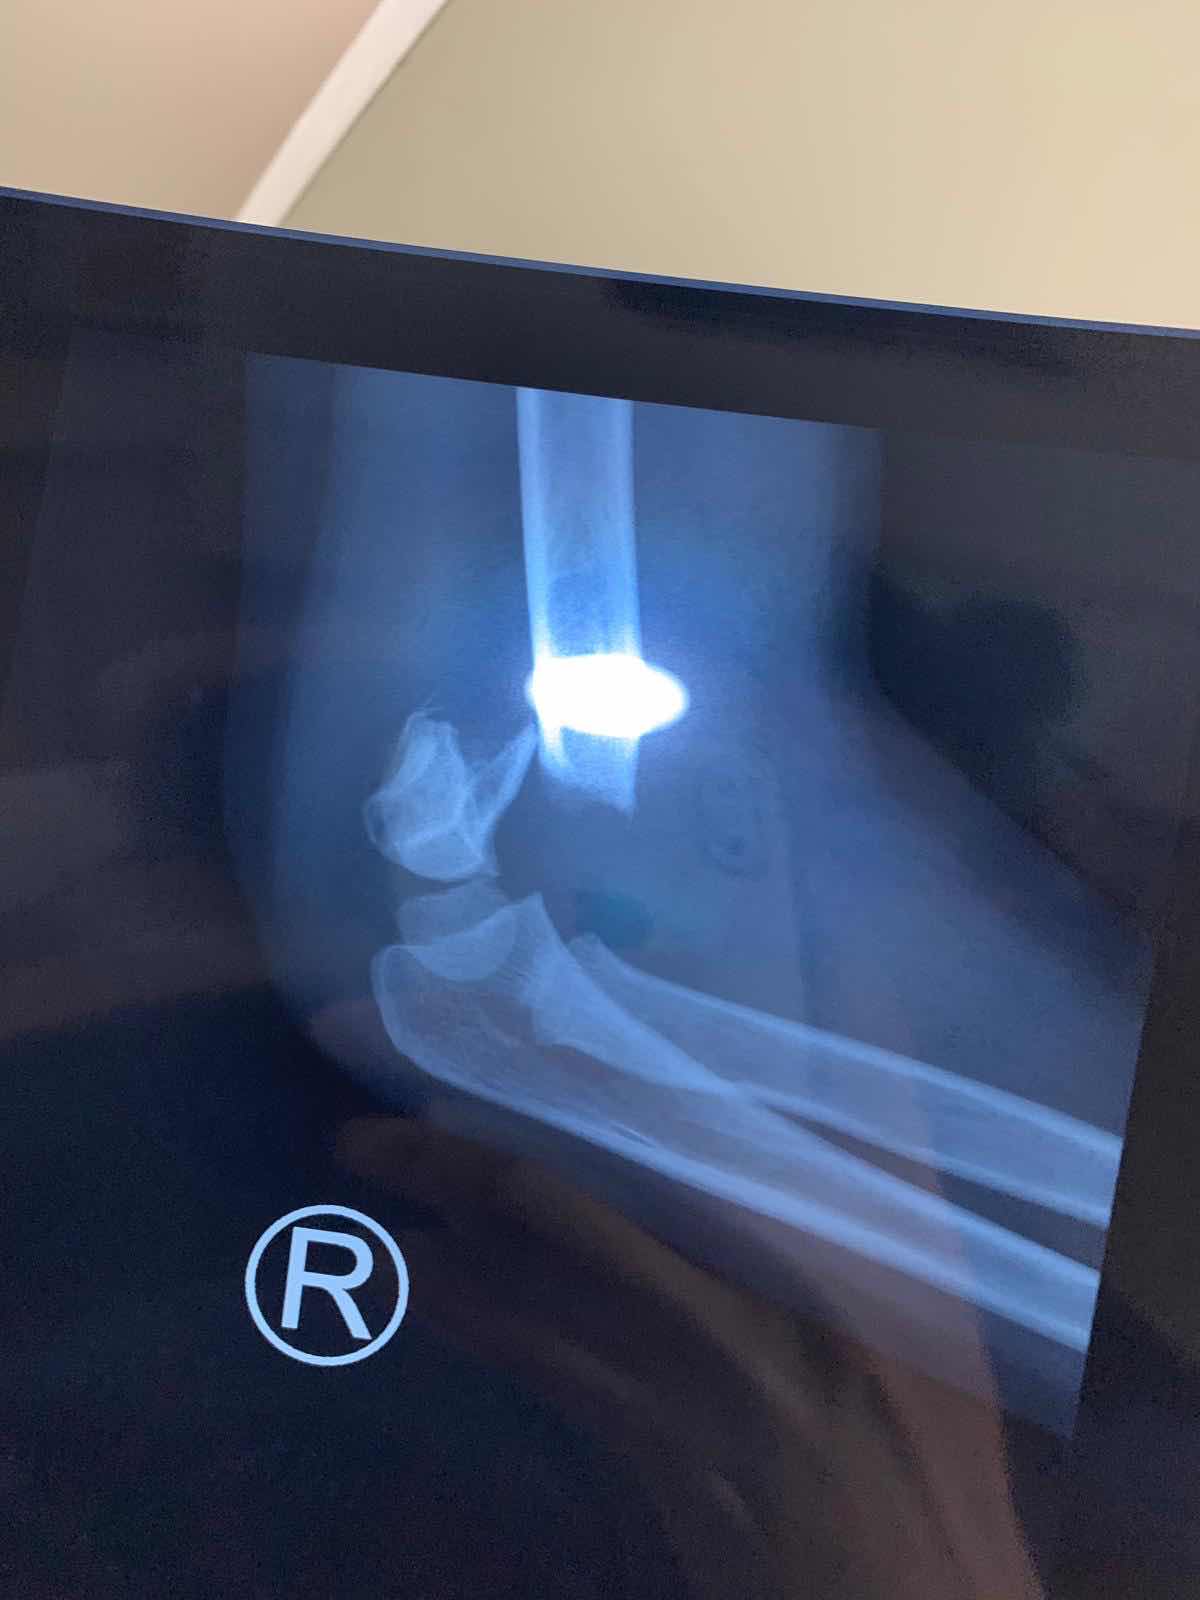

Now you can gasp. Not only is the bone now bones, the lower part is also twisted which could not be seen here.

Just out of surgery, little groggy. The little man had 3 wires inside him now.

So the doctor now said that he hasn’t seen such a serious case in 3 years and it’s the first time he put 3 wires instead of 2. I’m glad he didn’t say these before the surgery.

Bones in the right place now. Doctor said it could be better. But I’m already impressed that he moved them back in place without opening him up at all.